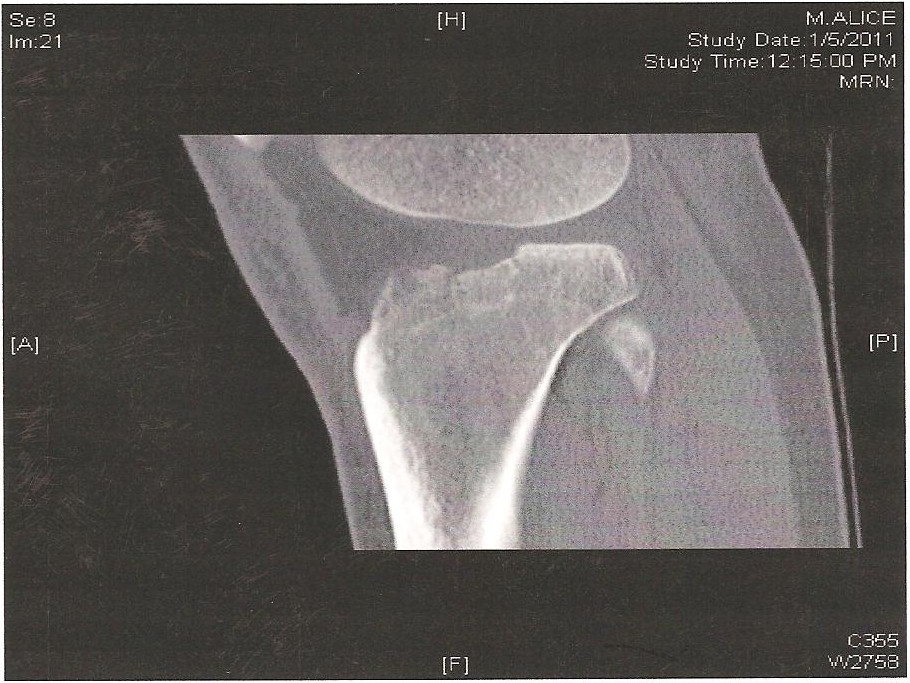

I flew home two days later and had surgery in Vail with the Womans US Ski Team doctor five days after I had broken my leg. Dr. Sterett put a plate and five screws to repair my tibia plateau. Basically what happened is when I was crashing my body moved forward with such momentum that my femur smashed my tibia plateau. I depressed the plateau by 8-9mm, so it was pretty messed up. Luckily the only ligament damage I had was my meniscus pulled apart from my tibia plateau so Dr. Sterett had to put in two stitches to reattach it to the bone.